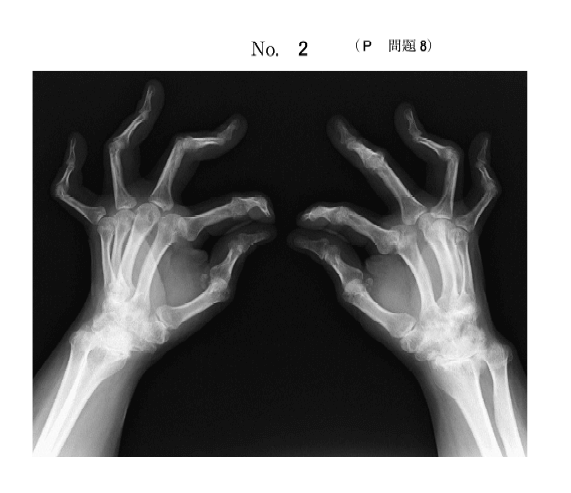

第52回国家試験 午前8

44歳の女性。関節リウマチ。エックス線写真を下図に示す。身の回りのことはできるが、仕事は行えない。

この患者のSteinbrocker の分類はどれか。